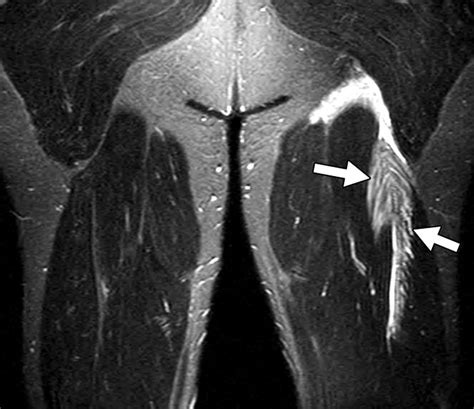

Anatomy and Function of the Pectineus Muscle

Anatomy of the hip and thigh

The pectineus is a flat, quadrangular muscle situated at the anterior aspect of the upper thigh. It acts as the bridge between the pelvis and the femur, functioning primarily as an adductor of the thigh and a flexor of the hip joint. Because it sits in the “groin” region, its involvement is frequently misidentified as a general groin strain.